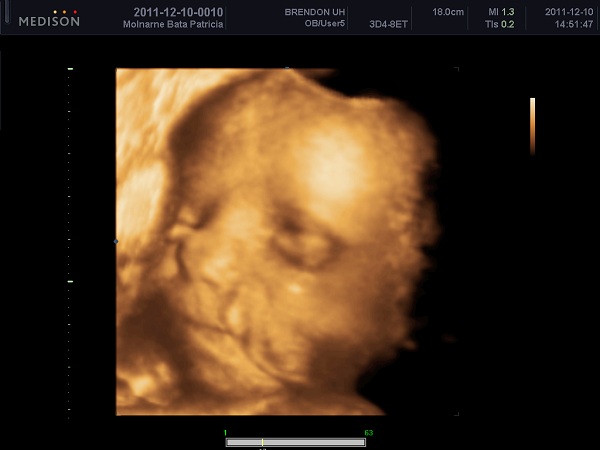

patricia83!

Jó lett nagyon a kép...

ti is biztosan látjátok ebből,hogy kire hasonlít...csodálkozom,hogy nem vették fel.engem még vissza is hívtak,amikor foglaltak voltak,és úgy próbálkoztam.